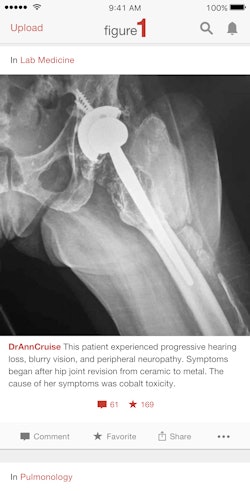

The image-sharing app Figure 1 has taken healthcare by storm since it launched in 2013, but the app's emphasis on mobile use didn't totally mesh with radiology's roots in computer workstations. New enhancements, however, may make Figure 1 even more useful for radiologists during their daily work.

Figure 1 allows physicians to upload deidentified images and photos of cases and get feedback and opinions from other users. Because cases are constantly uploaded, users can learn on an ongoing basis.

Landy noted that radiologists were probably the only group of Figure 1 users who didn't want to use their phones to capture images, and that radiologists have helped the company develop a lot of the features that are now a regular part of Figure 1's service. For example, the recently relaunched Web version of Figure 1 was built for radiologists and other physicians who use desktop computers.

In addition, Landy said that one of his favorite features on Figure 1's mobile app -- one that only applies to radiologists -- allows users to scroll through a stack of images by sliding a finger up and down the screen.

"You can now upload a full stack of CT or MR images on to Figure 1, and scroll through them like you would with a mouse [on a PACS workstation], but using your finger on a screen," he said.